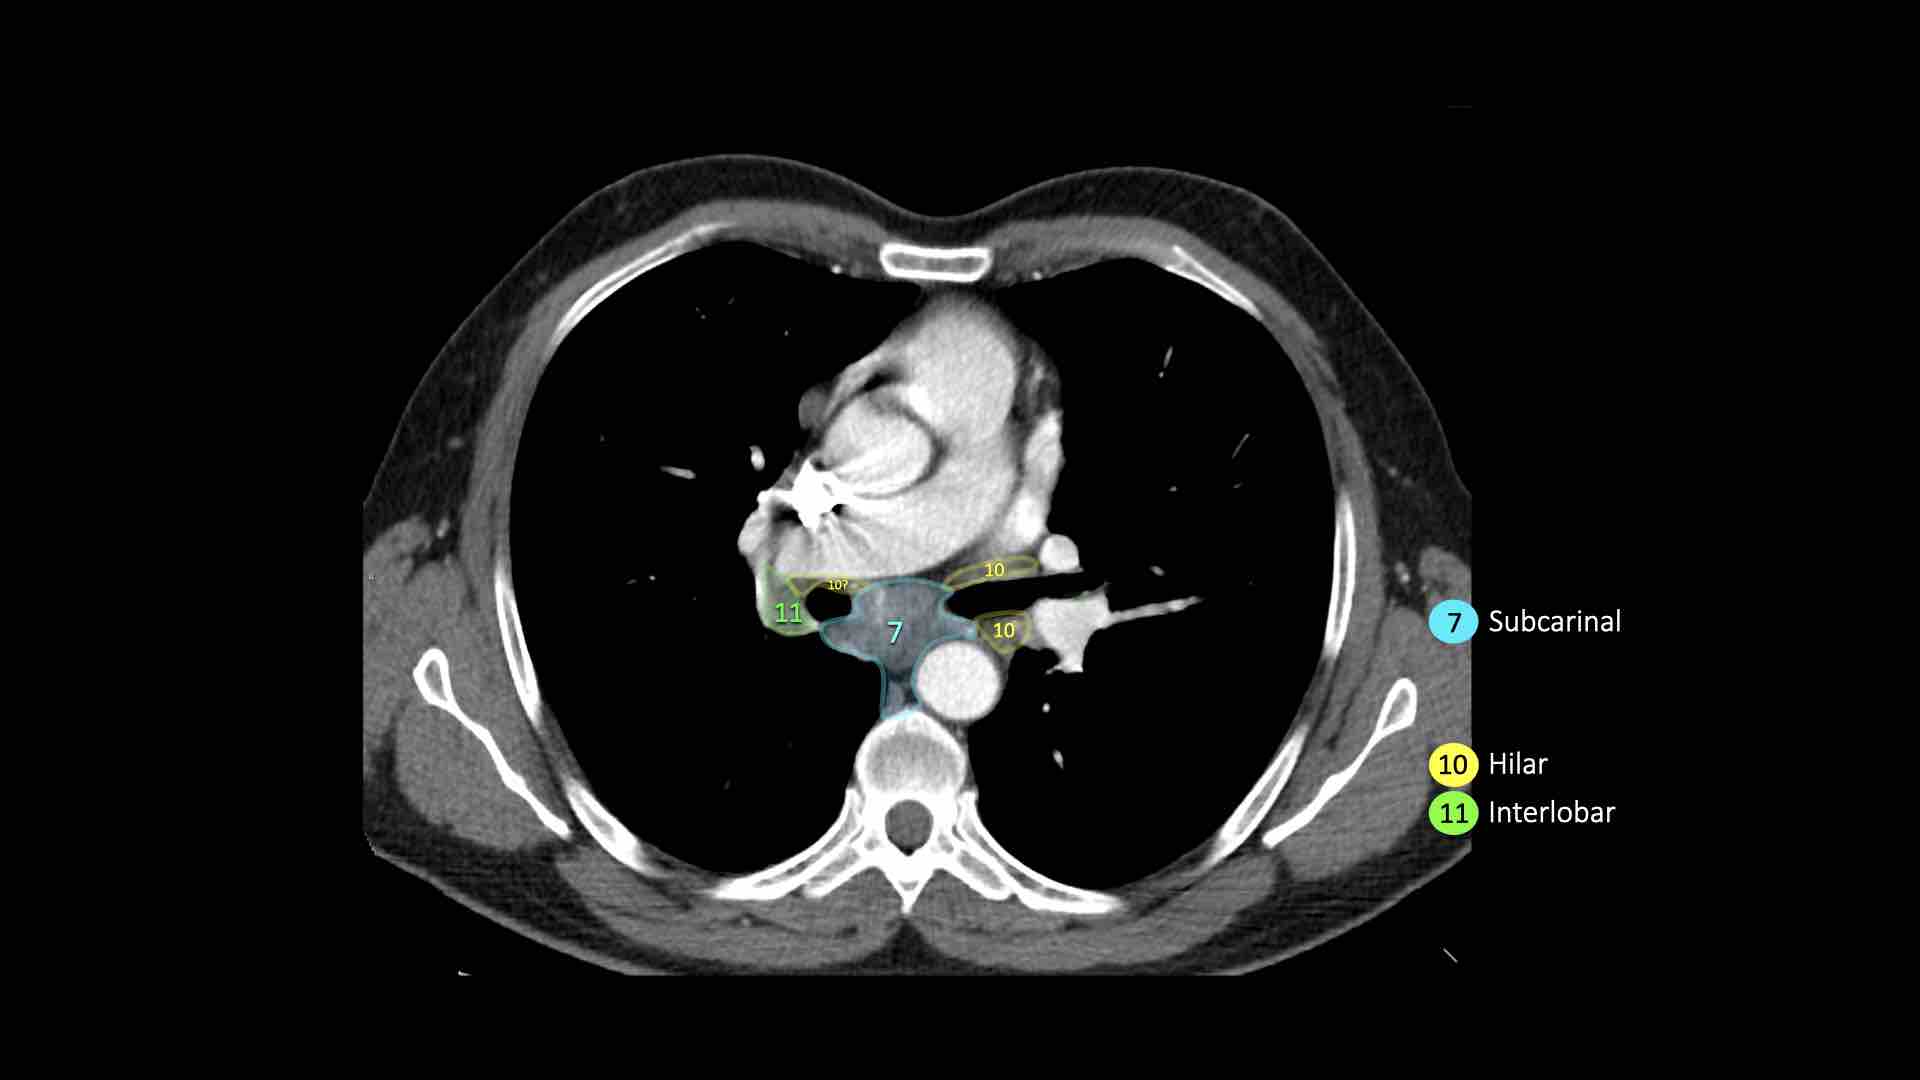

7. Hạch dưới carina

Các hạch này nằm ở phía dưới carina khí quản, nhưng không liên quan đến phế quản thùy dưới hoặc các động mạch trong phổi.

Bên phải, chúng trải dài xuống đến bờ dưới phế quản trung gian.

Bên trái, chúng trải dài xuống đến bờ trên phế quản thùy dưới.

Bên trái là hạch dưới carina nhóm 7 nằm bên phải thực quản.

10. Hạch rốn phổi

Hạch rốn phổi là các hạch thùy gần, nằm ở phía xa so với nếp gấp màng phổi trung thất và các hạch kề phế quản trung gian bên phải.

Các hạch từ nhóm 10 đến 14 đều là hạch N1, vì chúng không nằm trong trung thất.